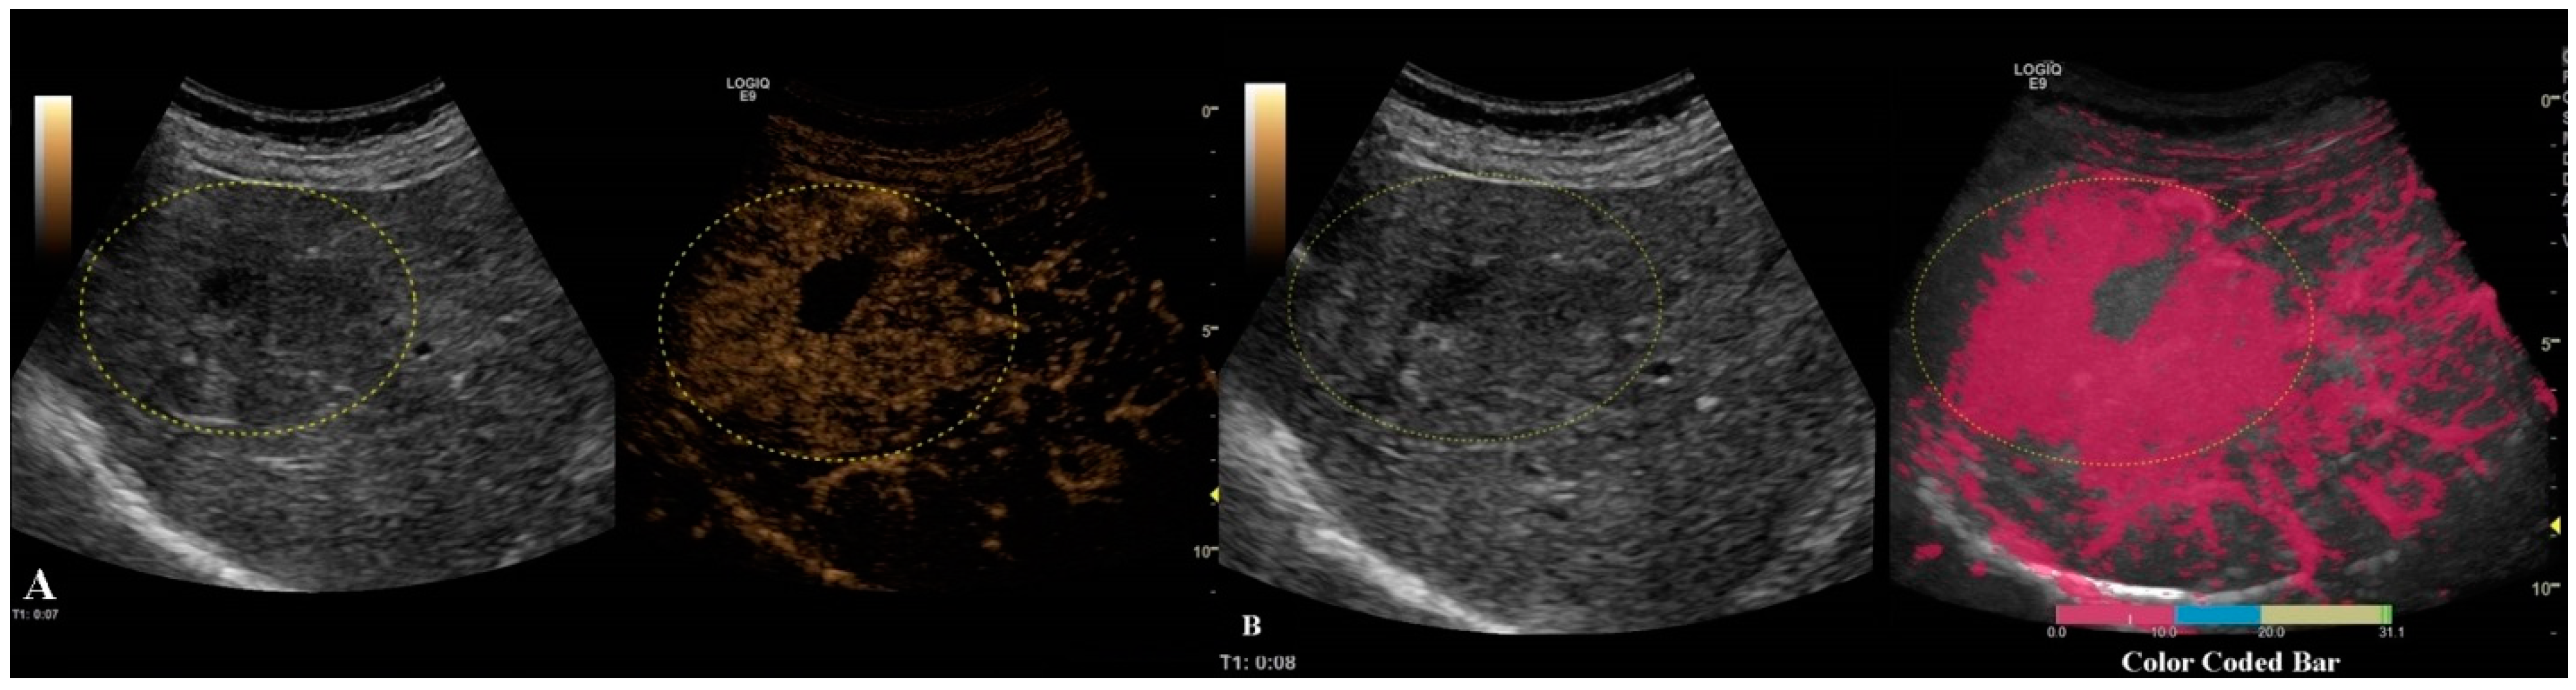

Different colors were used to define different arrival times, as shown in Figure 6. As a result, a color-coded map was superimposed over the B-mode image.

Figure 6.

Arterial phase of CEUS is depicted in frame (A). In frame (B), parametric imaging was applied, thus better documenting the arrival time of bubbles by using color coding, as shown in the color-coded bar.